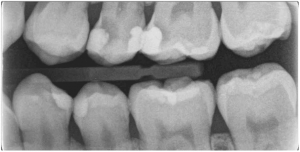

牙髓專科醫師會使用顯微鏡觀察牙齒,搭配 X 光片、3D 電腦斷層(CBCT)影像分析牙根結構、感染範圍與齒質剩餘量,並透過諮詢全面了解患者口腔狀況,協助規劃最合適的根管治療療程。

根管治療成功案例